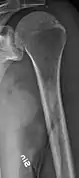

The diagnostic examination of a person with suspected multiple myeloma typically includes a skeletal survey. This is a series of X-rays of the skull, axial skeleton, and proximal long bones. Myeloma activity sometimes appears as "lytic lesions" (with local disappearance of normal bone due to resorption). And on the skull X-ray as "punched-out lesions" (pepper-pot skull). Lesions may also be sclerotic, which is seen as radiodense.[47] Overall, the radiodensity of myeloma is between −30 and 120 Hounsfield units (HU).[48] Magnetic resonance imaging is more sensitive than simple X-rays in the detection of lytic lesions, and may supersede a skeletal survey, especially when vertebral disease is suspected. Occasionally, a CT scan is performed to measure the size of soft-tissue plasmacytomas. Bone scans are typically not of any additional value in the workup of people with myeloma (no new bone formation; lytic lesions not well visualized on bone scan).

Multiple myeloma in the upper arm

Humerus with multiple myeloma lesions

Same humerus before, with just subtle lesions